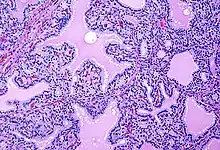

Biopsy to obtain histiological testing is not normally required, but may be obtained if thyroidectomy is performed.